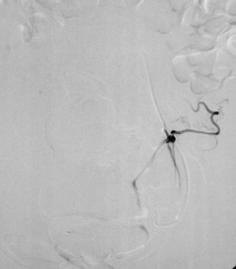

˨ÈûºóÂѳ²¶¯ÂöÏÔÓ°Ö®Ò»

˨ÈûºóÂѳ²¶¯ÂöÏÔÓ°Ö®¶þ

˨ÈûʱÂѳ²¶¯ÂöÏÔÓ° |

˨ÈûºóÂѳ²¶¯ÂöÏÔÓ° |